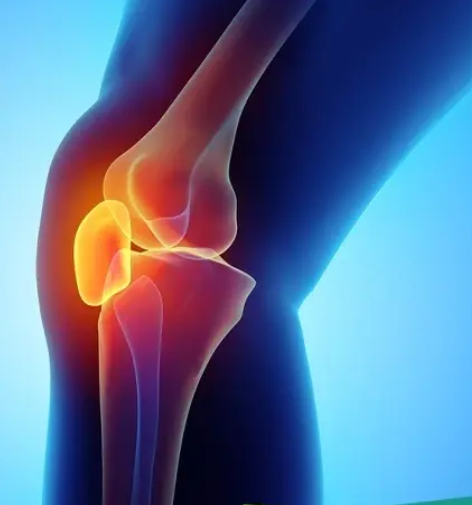

Chondromalacia Patella

Knee Bursitis

Anterior Cruciate Ligament Tear

Total Knee Replacement

Meniscal Injury

Patellar Fracture

Patella Dislocation

Medial Collateral Ligament Injury

Lateral Collateral Ligament Injury

Posterior Cruciate Ligament Injury

Popliteal (baker's) Cyst

Patellar Tendonitis

Knee Fracture

Knee Osteoarthritis